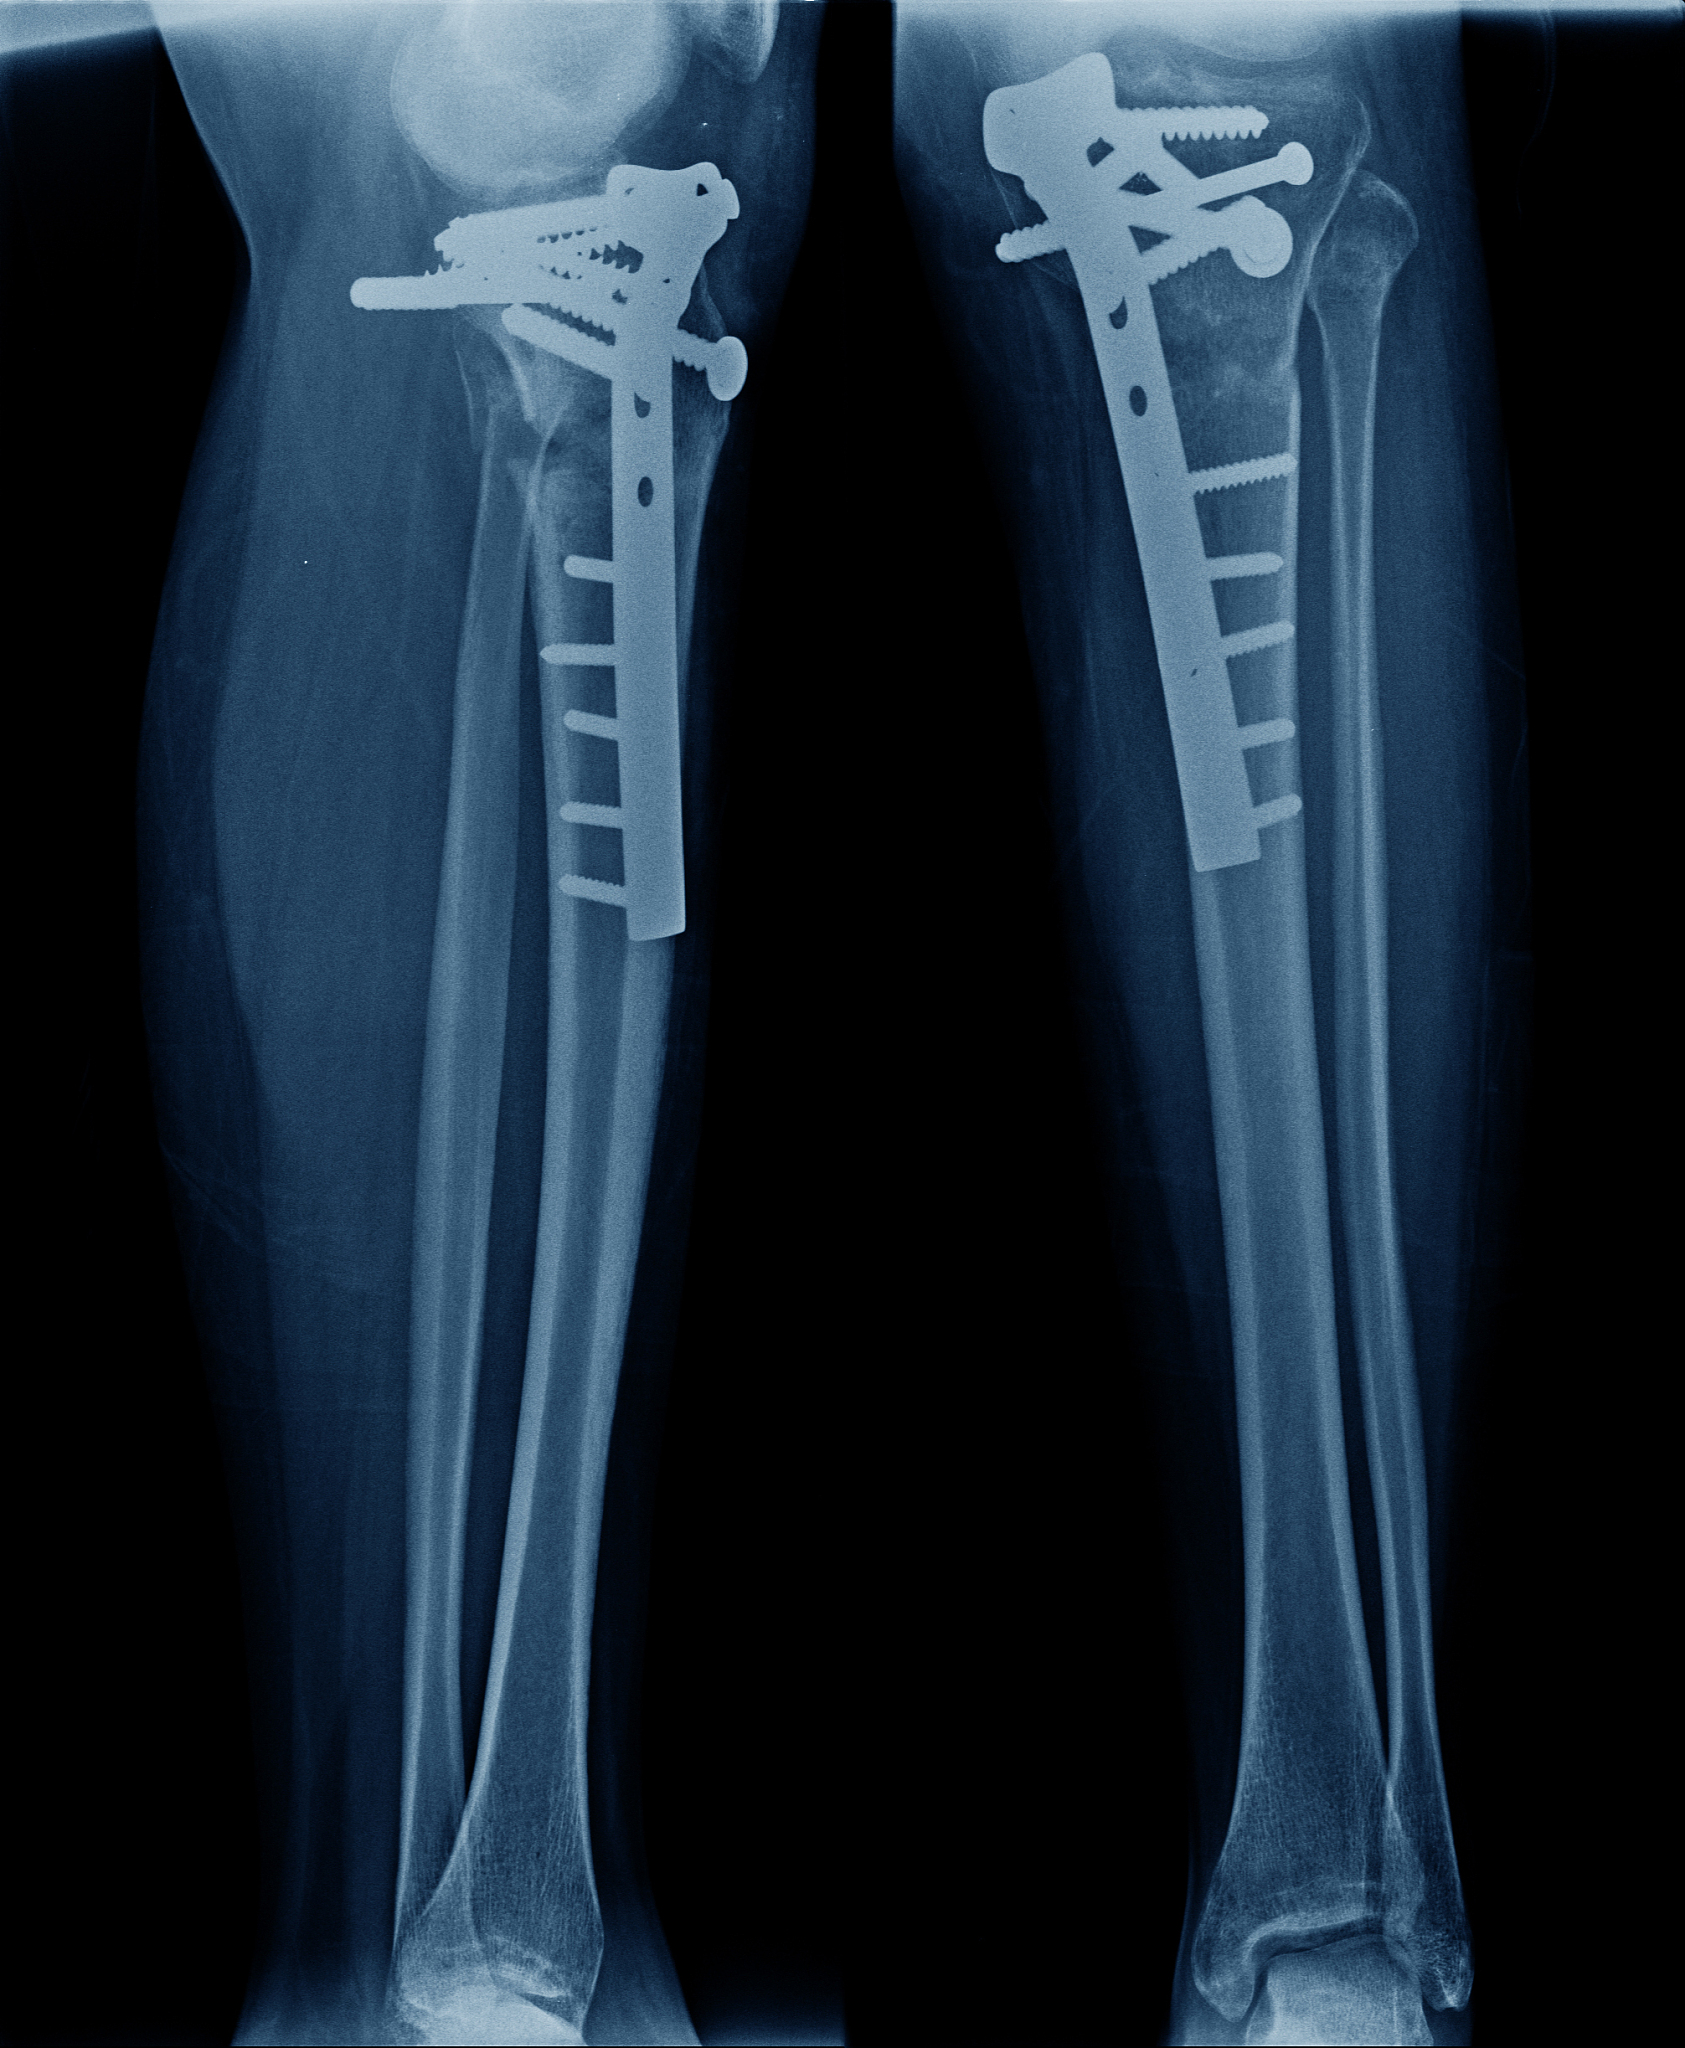

2. 影像学检查:X线是最常用的影像学检查方法,可以明确诊断胫骨平台骨折及其类型。后外侧塌陷的胫骨平台骨折通常表现为胫骨平台的后外侧部分向下塌陷,形成一个凹陷或凹槽。有时候,CT扫描可能需要用于进一步评估骨折的复杂性和伴随的软组织损伤。

3. 分类和治疗:胫骨平台骨折按Schatzker分类可分为6个类型,其中后外侧塌陷的骨折通常属于类型V或VI。治疗方法包括保守治疗和手术治疗。保守治疗适用于骨折稳定、无明显移位或老年患者。手术治疗常常需要进行骨折复位、内固定和修复软组织损伤。